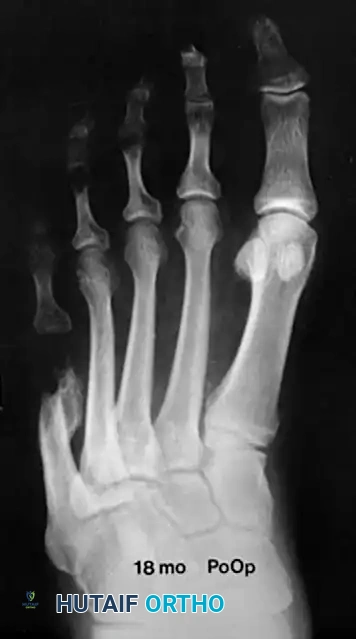

Partial resection of the lateral condyle of the fifth metatarsal head is historically the most commonly utilized procedure. It effectively relieves pressure symptoms and allows the patient a slightly greater variety of shoe wear. However, the cosmetic correction is not always pleasing, and patients must be counseled accordingly.

The patient must be explicitly warned before surgery that only the painful bony prominence will be removed. The overall width of the forefoot will not be altered appreciably. If forefoot narrowing is the primary goal, an osteotomy is required.

Causes of failure in lateral condylar resection include inadequate resection, MTP joint subluxation, and progressive forefoot splaying. Furthermore, if there is a painful callosity beneath the metatarsal head, the plantar aspect of the condyle must also be removed to prevent persistent plantar pain.

Associated Surgical & Radiographic Imaging